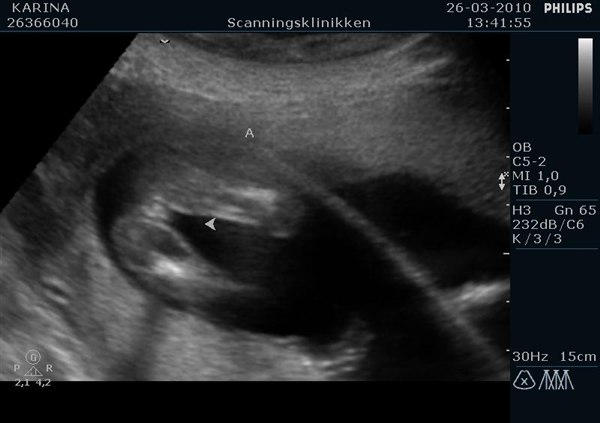

Vial

Det er jo rigtig svært at se for det utrænede øje.

Meeen i og med at der er samme køn og scanningsdamen mener, at begge kunne være drenge, så er det nok to små knægte.

Har I tænkt på navne endnu?

Du kan lige se mine babyers køn fra da de var 16+6. Havde jeg ikke vidst det, så kunne jeg da ikke se forskel...kan du?

Vedhæftede fotos (klik for at se i fuld størrelse)

den er ikke nem men drengen er nemmere at se end pigen må jeg sige. Men mine må jo være drenge så, men tøt ik helt tro det før vi har fået det tjekket igen på tirsdag hehe